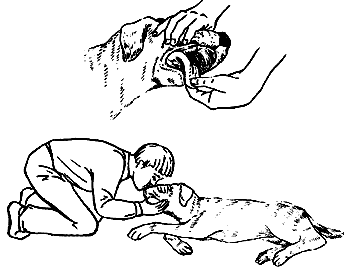

Искусственное дыхание и массаж сердца

Сначала нужно положить собаку на правый бок на ровную поверхность, удалить слизь и посторонние предметы из пасти животного и осторожно вытащить наружу язык, чтобы облегчить поступление воздуха в легкие.

Искусственное дыхание для собаки осуществляется практически так же, как и для человека. Несколько секунд необходимо ртом вдувать воздух в ноздри собаки, затем делается перерыв на несколько секунд. Повторять процедуру следует не один раз, иногда на восстановление нормального дыхания может потребоваться около 1 ч.

Искусственное дыхание следует чередовать с массажем сердца. Положив руку на грудь собаки за локтем, необходимо осуществлять ритмичные и быстрые надавливания, ни в коем случае не допуская перерывов более чем на 5 с. В 1 мин должно производиться приблизительно 60 надавливаний. Общая продолжительность процедуры составляет 10 мин. Если работа сердца не восстанавливается, это означает смерть животного. Положительный эффект описанных мероприятий определяется по следующим признакам: восстановление дыхания и нормального сердечного ритма, пульс животного прощупывается, а зрачки сужаются и начинают реагировать на свет.

Искусственное дыхание

Если животное находится в бессознательном состоянии, важно как можно скорее приступить к осуществлению необходимых мероприятий.

Применять искусственное дыхание и массаж сердца необходимо в течение 2–3 мин после остановки сердца и дыхания. Также можно попытаться восстановить дыхание у собаки, резко ударяя ладонями плашмя по груди животного, но делать это следует тотчас после потери сознания.

Если вы заметили, что десны животного постепенно розовеют (у собаки в бессознательном состоянии они бледные), это является первым признаком восстановления нормальной дыхательной функции организма.